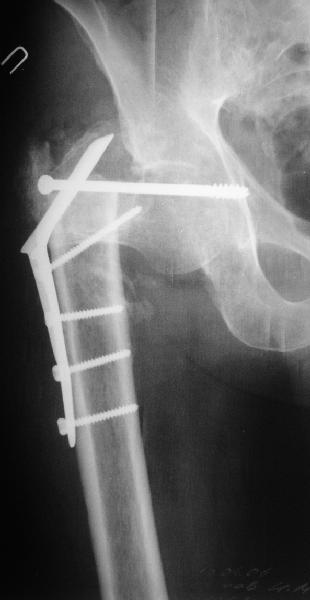

В приложении пример пациента, близкого по картине к тому, что представил Виктор (варус и смещение периферического отломка на поперечник кзади). Сделали как раз то, что Виктор исходно намеревался - аппаратная коррекция и затем гамма.

Если судить по снимкам, то укорочение кажеться не критическим, но обьективно и на 3D - укорочение на 6-7 см.

Думаю сделать так: под адекватной анестезией на тракционном столе попробую максимально низвести бедро. Если получится, рентгенконтроль/оценка ситуации и Blade Plate с костной пластикой (помню предостережение Александра Николаевича о возможной варусно-антекурвационной установке центрального отломка и трудности в использовании Гамма-гвоздя). Если останется укорочение на 3-4 см придется на короткое время (2-2,5 недели) наложить стержневой аппарат "бедро-бедро" и дробно, но форсированно, ориентируясь на ощущения больного и поведение дистальных отделов конечности адаптировать отломки (больной на это период останется в стационаре). Если же появятся первые признаки воспаления мягких тканей в области проксимальных стержней, аппарат снимаю, перевожу на скелетное вытяжение и готовлю больного ко второму этапу.